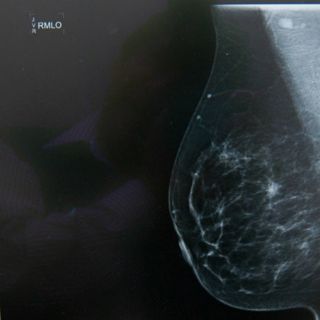

Esta prueba es un pretamizaje para una detección oportuna, sin embargo, no sustituye a la mastografía, solo es un complemento a este examen, precisó.

"La mastografía sigue siendo el tamizaje por excelencia y los resultados son marcados; no obstante, sí podemos hacer una selección de grupos de riesgo para enviar posteriormente a mastografía si tienen una cantidad elevada de micronúcleos en sus células de mucosa bucal", comentó.